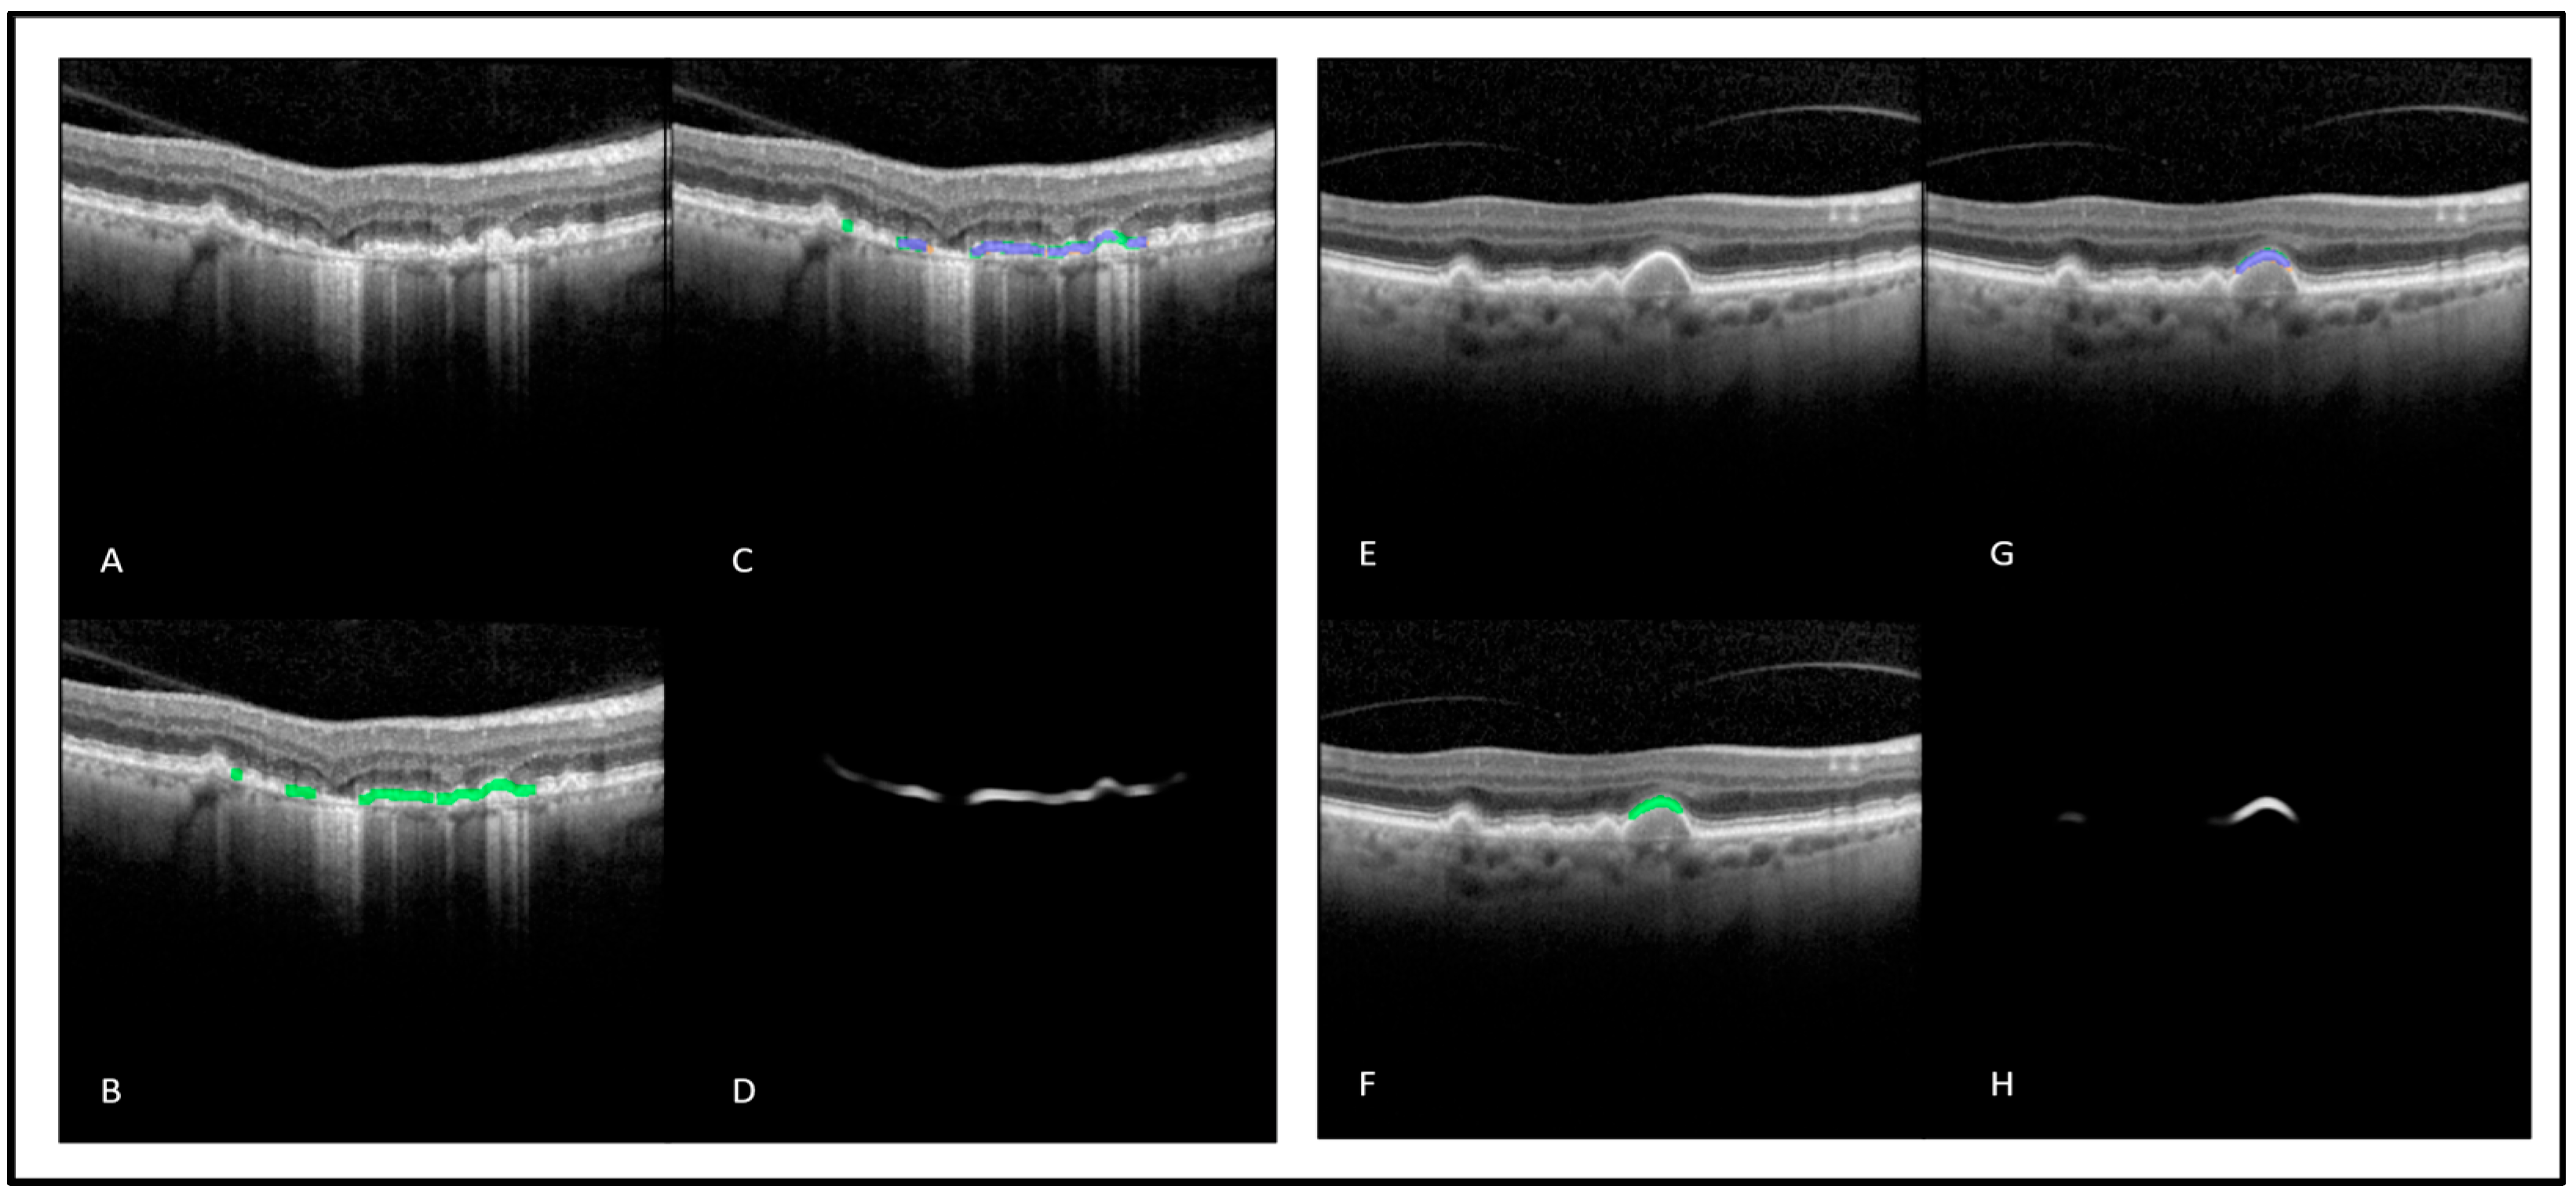

3.1. DL-Based Automated Detection and Measurement of Regions with EZ At-Risk